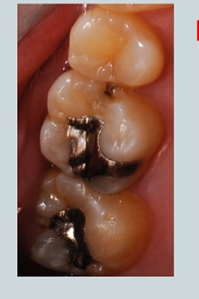

spot the caries

lower right and left second molars

are they the same colour? - the lower right has a fissure sealant

black one indicates staining and possible caries